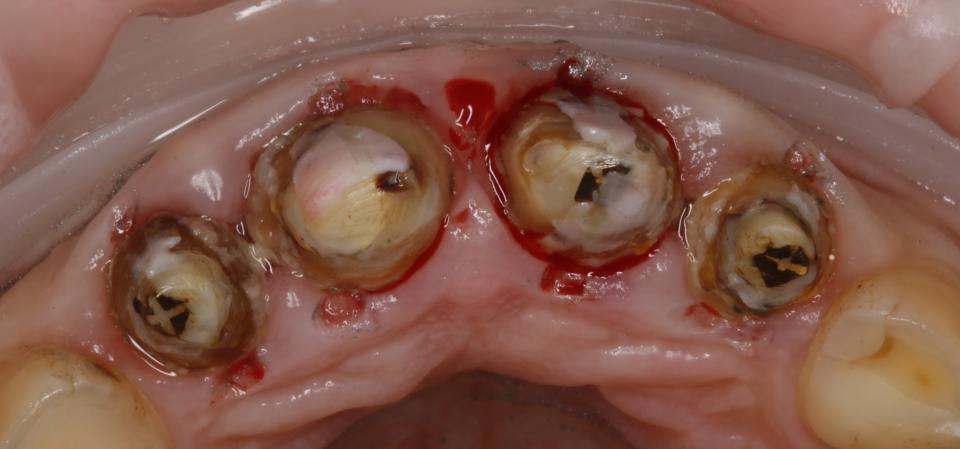

paraschyk1 Опубліковано: 6 червня 2018 Автор Опубліковано: 6 червня 2018 Вот фото зубов где коронки были сделаны пять лет назад с прайсом вдвое дороже чем у меня сейчас. Зубы после такого- трупы.А все от ненадлежащего качества работы и пох.зма в отношении в людям.

paraschyk1 Опубліковано: 6 червня 2018 Автор Опубліковано: 6 червня 2018 Вот фото где также коронки простояли четыре года и пац только выплатил кредит по ним,а спустя два мес. пришлось все убрать и переделывать,ессно за новые тугрики.